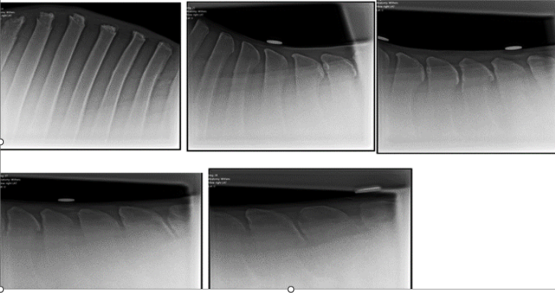

7 years ago I bought a beautiful unbacked broodmare aged 7 and backed her. She had had a couple of foals. She started playing up when ridden so we investigated and asked questions of previous owners. It turns out she had had an accident as a yearling and had a rotational fall over a fence. Hence broodmare. On investigation, we found a scarred tendon and two places where spinal process touched with boney remodelling (white bits on xray). We rehabbed her, steroid injections, didn't operate though. She was never happy ridden, so retired 6 years ago. She has recently developed slight lameness in front and after vet investigations, has been diagnosed with navicular. As part of the investigation, I asked the vet to xray her spine. Spine now shows no kissing spine, no touching, no bony remodelling or white! How about that!